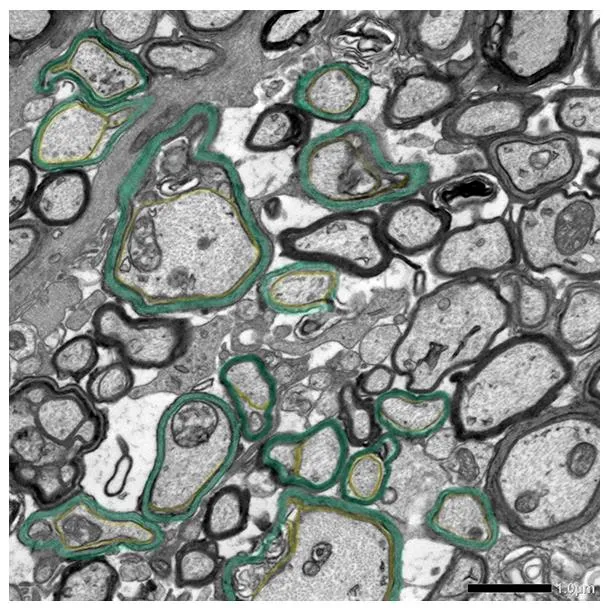

Dioprotectrome™ treated

Repair of coating around nerve fibres

(remyelination) and neurological recovery

Repair of coating around nerve fibres(remyelination) and neurological recovery